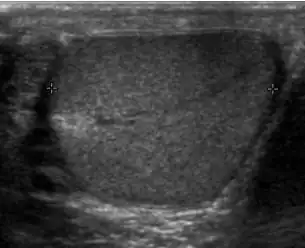

Patients with testicular lymphoma are usually old aged around 60 years of age, present with painless testicular enlargement and less commonly with other systemic symptoms such as weight loss, anorexia, fever and weakness. Bilateral testicle involvements are common and occur in 8.5% to 18% of cases. At sonography, most lymphomas are homogeneous and diffusely replace the testis [Fig. 7]. However focal hypoechoic lesions can occur, hemorrhage and necrosis are rare. At times, the sonographic appearance of lymphoma is indistinguishable from that of the germ cell tumors [Fig. 8], then the patient's age at presentation, symptoms, and medical history, as well as multiplicity and bilaterality of the lesions, are all important factors in making the appropriate diagnosis.

At ultrasound, the findings of acute epididymitis include an enlarged hypoechoic or hyperechoic (presumably secondary to hemorrhage) epididymis [Fig. 20a]. Other signs of inflammation such as increased vascularity, reactive hydrocele, pyocele and scrotal wall thickening may also be present. Testicular involvement is confirmed by the presence of testicular enlargement and an inhomogeneous echotexture. Hypervascularity on color Doppler images [Fig. 20b] is a well-established diagnostic criterion and may be the only imaging finding of epididymo-orchitis in some men.